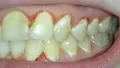

Волнуют мои зубы. Мне кажется, что мои зубы находятся в крайне запущенном состоянии. Как привести мои зубы в приемлемый вид? Мне кажется, что запломбированные зубы плохо выглядят. На верхней левой четверке выпала пломба.

Ваши зубы скорее всего требуют срочного лечения. Где-то возможно хроническое воспаление (периодонтит), а где-то и пульпит (воспаление нерва).